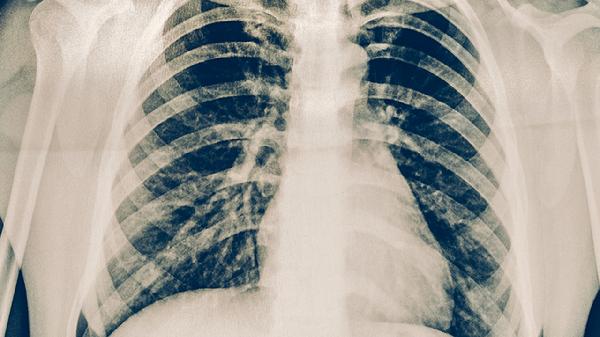

肺結(jié)核患者需遵循高蛋白、高熱量、高維生素的飲食原則,適量補充富含優(yōu)質(zhì)蛋白、維生素A/C/D及鈣鐵鋅的食物,避免辛辣刺激、酒精及生冷食物。主要飲食指導(dǎo)包括分論點a、分論點b、分論點c、分論點d、分論點e等。